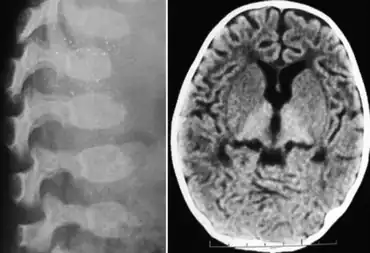

| GM1 gangliosidosis-X-ray indicates dysostosis multiplex at lumbar region and scan of brain indicates hyperdense thalamus | |

- Skeletal deformities: flexion contractures noted by 3 months; early subperiosteal bone formation (may be present at birth); diaphyseal widening later; demineralization; thoracolumbar vertebral hypoplasia and beaking at age 3–6 months; kyphoscoliosis. *Dysostosis multiplex (as in the mucopolysaccharidoses)